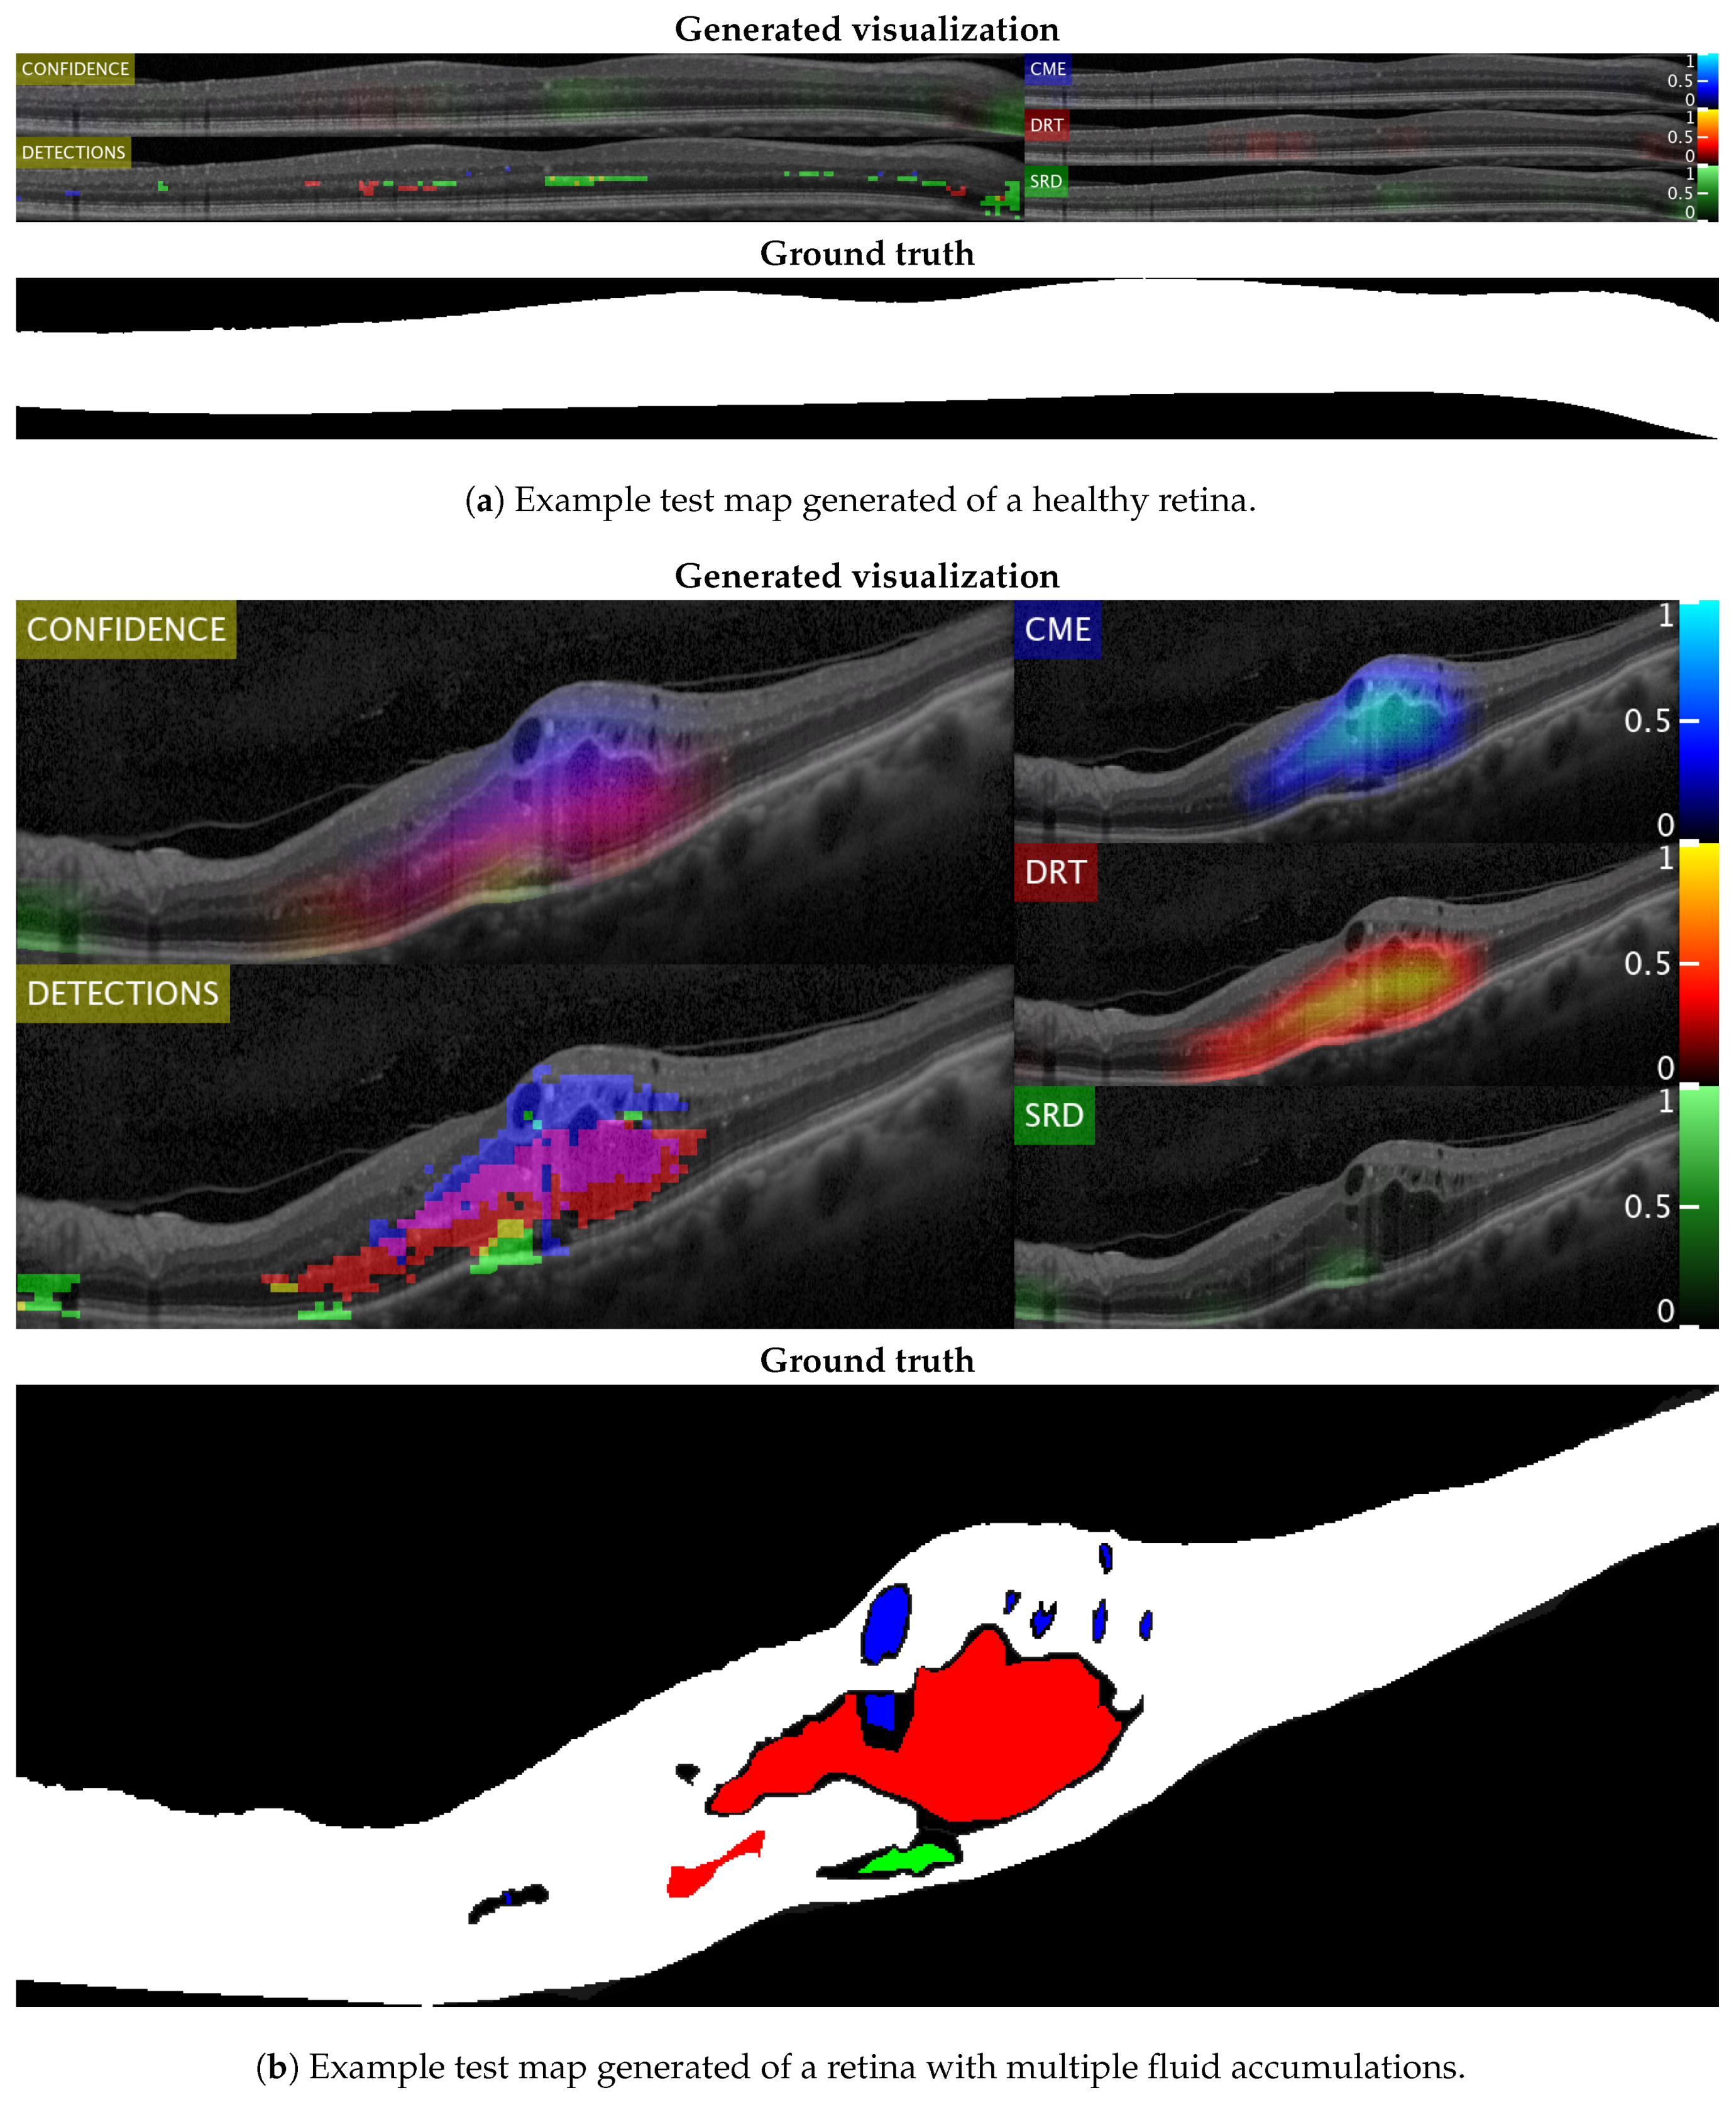

Figure 14 and Figure 15 show representative examples from the test set with a healthy image and another one with different types of pathological fluid generated with the Spectralis and Cirrus devices, respectively. In addition, the labels of the expert are included to compare with the results. As can be seen, in both cases, the system is capable of satisfactorily detecting the pathological fluid accumulations whenever they are present, although we can see spurious detections in the cases of both Figure 14a and Figure 15a. However, these detections can be easily corrected with post-processing strategies as mentioned before, but we decided to include them for a better understanding of the behavior of the system.

Figure 15.

Test visualizations generated using images from the Cirrus device.

In these visualizations, we can observe two major phenomena. The first one consists in the tendency to spurious detections in the images generated by the Spectralis of the SRD-type edema. This may be due to the higher contrast of the images generated by this device, favouring the appearance of common patterns of the SRD-type edema not present in the images that are generated with Cirrus. On the other hand, we can see a clear tendency in the Cirrus images to generate small detections of DRT-type edema. This is due to what was already mentioned in the section where we analyzed the selection of features: the DRT pattern of the images that are generated with the Cirrus device is very similar to the normal tissue in comparison with the "wet" and coarse texture of the DRT fluid accumulations in images that are generated with the Spectralis device.

In the images that were used for testing, we have found an example of each of these extreme cases, represented in Figure 16. In this figure, we see the particular case of an Spectralis image with dark regions detected as SRD (Figure 16a) and a particular case of a Cirrus image with slightly thickened layers that was detected as DRT (Figure 16b).

Figure 16.

Representative visualizations from both devices with visible misclassifications.